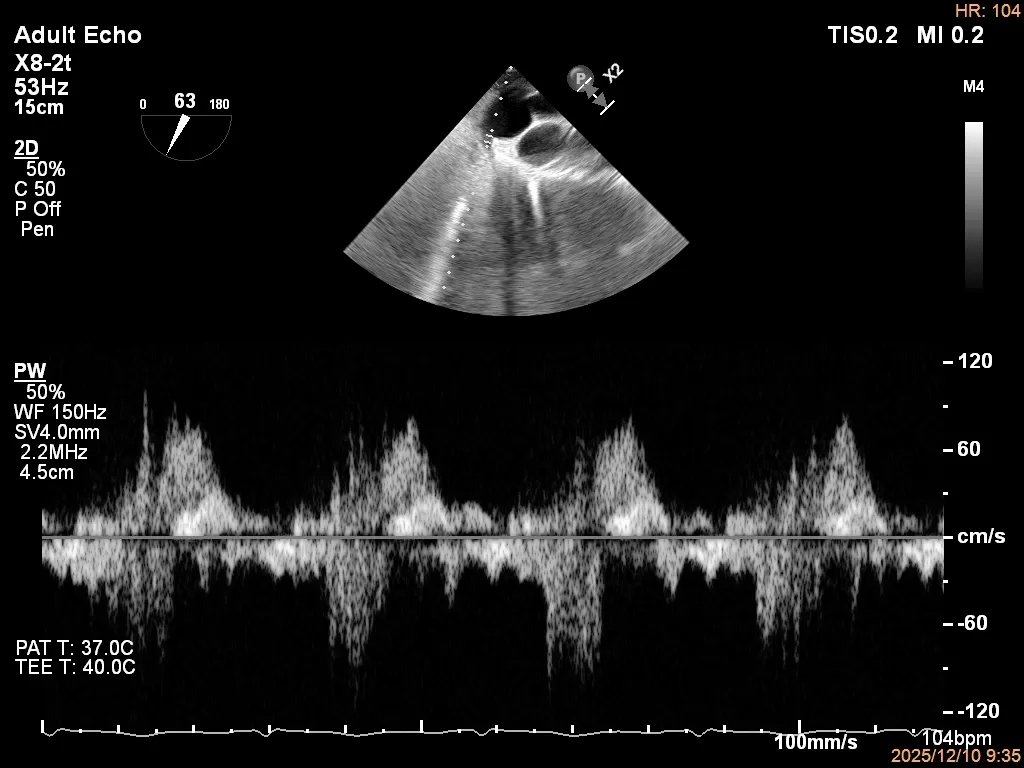

术后影像

最终结果3D-Zoom-color显示组织桥稳定,原脱垂区域前后叶对合部分的脱垂已消除,反流降至1+以下

夹子释放Bi-com切面显示残余反流情况

肺静脉收缩期逆流消失,频谱形态基本恢复正常

术后2D TTE:

术后TTE可见二尖瓣微量-轻度反流,三尖瓣反流明显改善降至中度